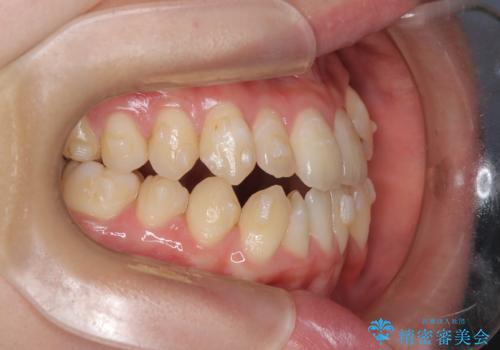

診査の結果、すでに下顎前歯の抜歯が行われていましたが、マウスピースの適合が著しく悪くなっており、歯が計画通りに動いていない状態でした。また、歯を支える骨の厚みや歯肉の薄さを考慮すると、このままマウスピースによる傾斜移動を続けるのは歯肉退縮(歯茎が下がること)のリスクが非常に高いと判断。

装置の変更と歯肉への配慮: ワイヤー矯正は歯の根(歯根)を平行に移動させる「歯体移動」を得意としています。本症例では、歯肉退縮を防ぐために、歯の傾きを精密にコントロールしながら抜歯スペースを閉じる必要がありました。ワイヤー装置を用いることで、インビザラインでは難しくなっていた三次元的な細かい調整を可能にしました。

リカバリーのプロセス: 適合が悪くなったインビザラインを一旦中止し、ブラケットを装着。停滞していた歯の移動を再開させ、上下の正中(中心)や奥歯の咬み合わせを一つひとつ整えていきました。